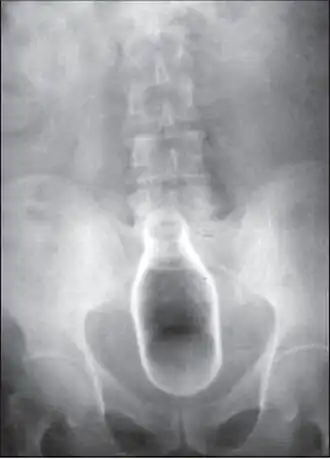

Стеклянная бутылка в просвете прямой кишки на рентгенограмме | |

Обычно делают несколько рентгеновских снимков, чтобы точно определить место нахождения инородного тела. Инородные тела из малоконтрастного материала (например, пластика) могут потребовать ультразвукового исследования или компьютерной томографии.[28] Магнитно-резонансная томография противопоказана, особенно если неизвестен материал инородного тела. Инородные тела прямой кишки могут проникать глубоко в толстую кишку, при определённых обстоятельствах вплоть до правого изгиба ободочной кишки.[9]

| Стеклянная бутылка | Биопсийные щипцы | Общая | [32] |

| Стеклянная бутылка | Присоска | Общая | [28] |